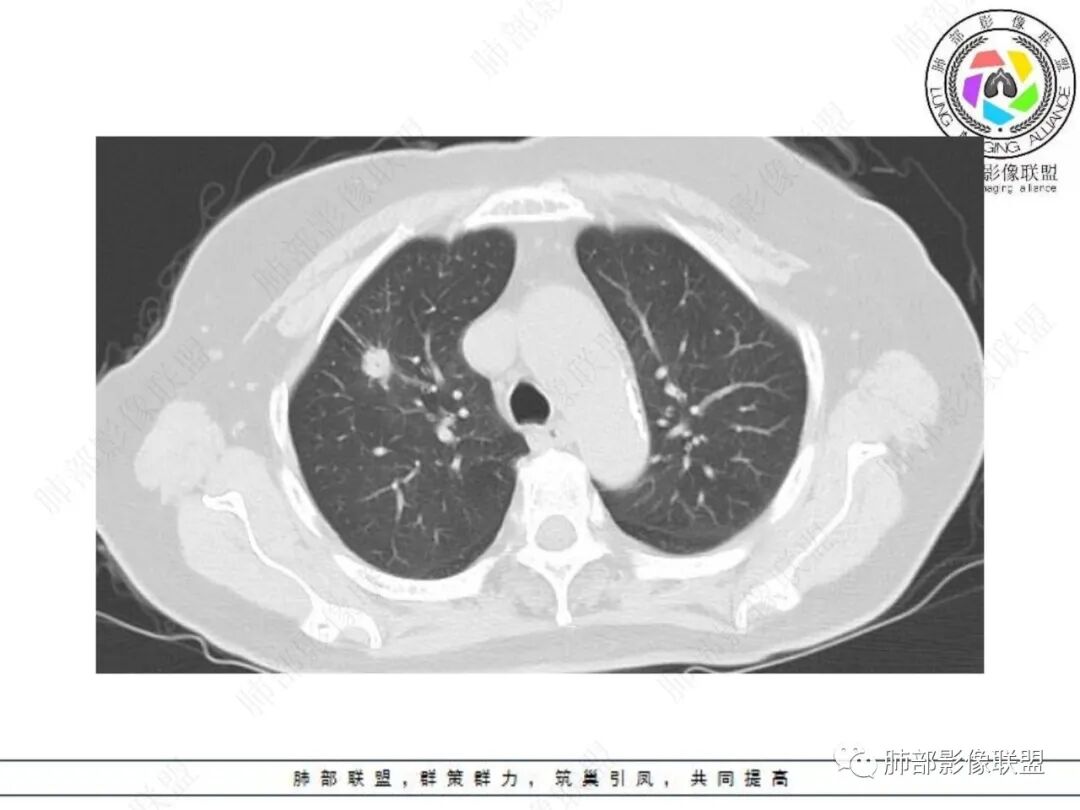

老年女性,体检发现,无呼吸道症状。右肺上叶尖段孤立性实性结节,下份见空泡,余密度较均匀。病灶形态不规则,边缘多膨隆,可见浅分叶及细毛刺,血管集束,未能显示相关支气管情况。病灶胸膜侧见小锯齿状凸起、胸膜牵拉及兔耳征,结节前缘见磨玻璃影,磨玻璃影边界较清楚(需薄层确认),结节外侧见指状凸起影。未见卫星病灶,纵隔窗未见明显钙化。增强扫描:较明显渐进性强化。

2.病例分析:

老年女性,右肺上叶孤立实性结节,边缘欠光整,强化明显,未见卫星灶,已经让人高度警惕恶性肿瘤,尤其是腺癌!

浸润性腺癌支持点还有空泡及磨玻璃晕,但非薄层图像,磨玻璃影表现可靠性降低。

病灶张力不高,磨玻璃晕等需要鉴别隐球菌感染或其他炎性肉芽肿,虽然位置并不靠近胸膜。肺腺癌与隐球菌感染的鉴别,在影像学上也许是个永恒的话题。

没有卫星灶,没有树芽征,没有新旧不等,强化明显等不支持继发性肺结核。结节影边界欠光整,缺乏游离感,没有脂肪密度或钙化,强化特点等都未能显示出硬化性肺细胞瘤或者错构瘤的影像学特点。

浸润性腺癌:多见于老年女性。结节深分叶,收缩力强,磨玻璃影边界清晰,且磨玻璃影内部缺乏结节感。另外CT特点可有如下:空泡征及“假大空”,"月牙"征与“L”形缺口,胸膜牵拉凹陷,支气管充气征与支气管牵张扭曲,分叶征,毛刺征,膨胀边缘与胸膜处锐角,血管穿行征等。—摘自《普通型肺腺癌CT特征的病理解释》王兆宇老师